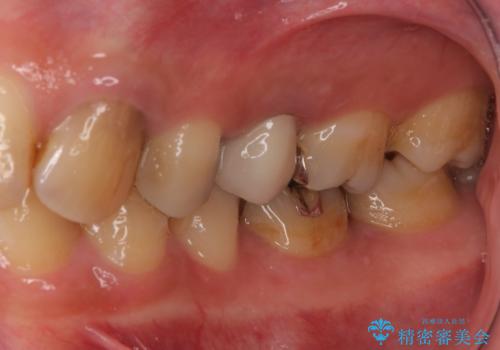

ご来院当初、患者様は1番奥歯のセラミック治療をご希望されてました。しかし、しっかり診査をして1本手前の歯を治療した方が良いとご提案させて頂きました。

また、奥歯が虫歯になりやすい原因として夜間の歯ぎしりで、歯に小さいヒビが入っている疑いがありました。就寝時マウスピースを使用して予防して頂くこともご提案し、患者様には大変満足して頂きました。